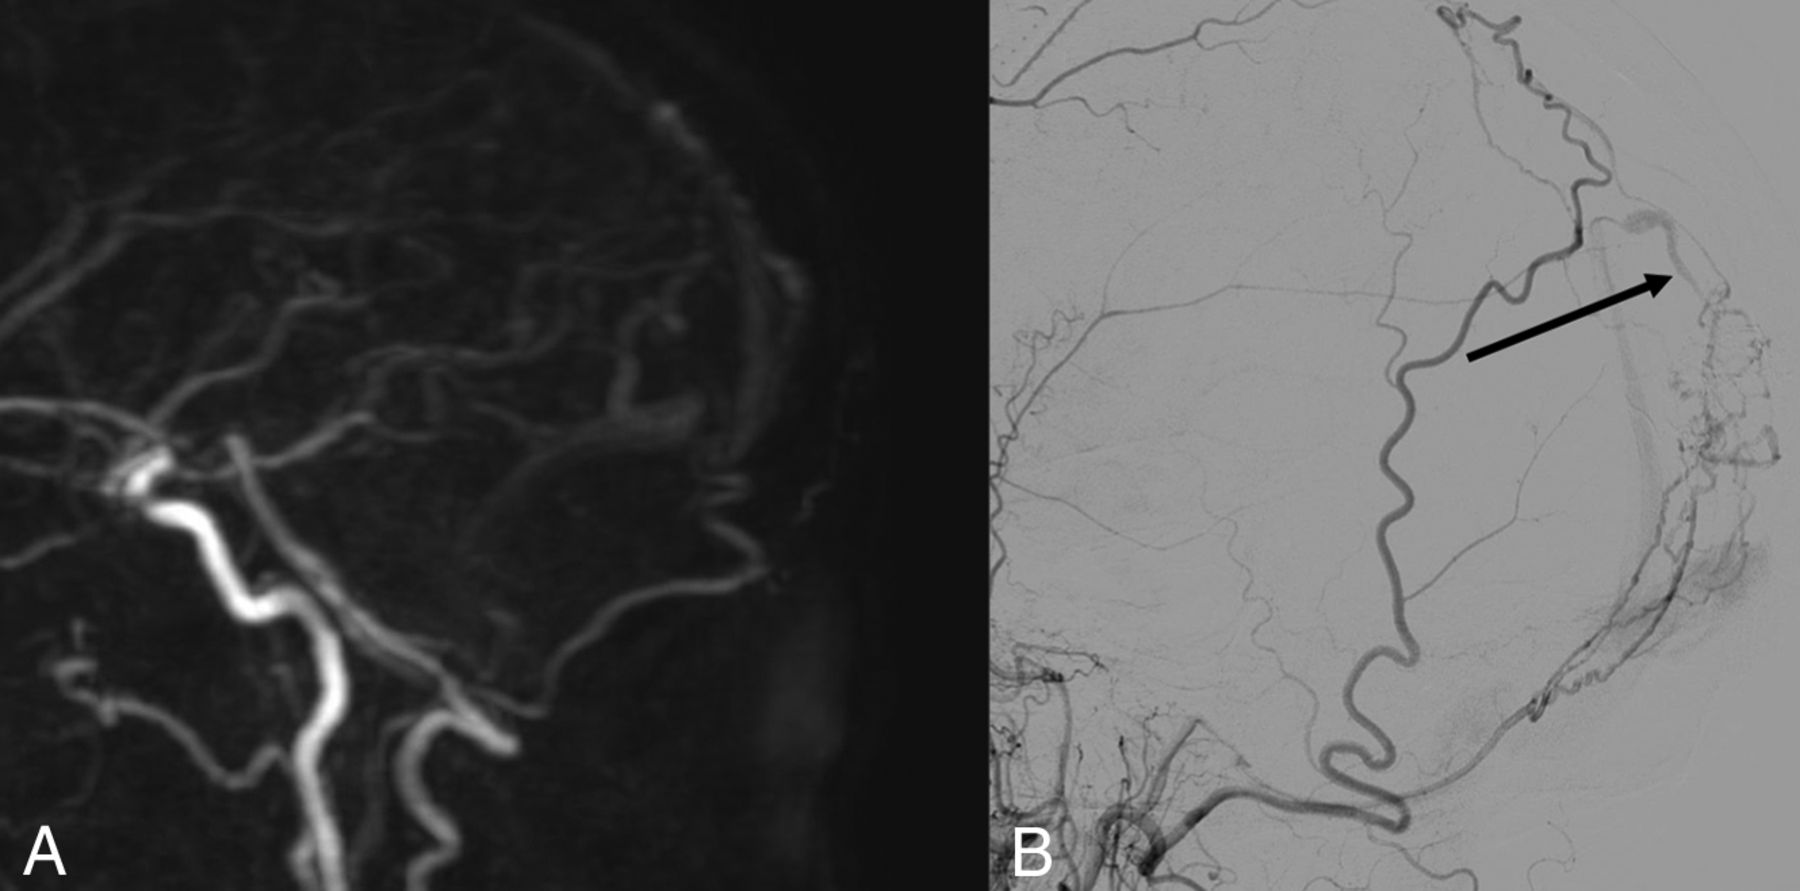

A, Sagittal MIP of 4D-MRA at arterial phase. B, Cerebral arteriography through the left vertebral artery in a sagittal view. The white arrow in A and the black arrow in B show early opacification of an epiphyseal vein, before the superior sagittal sinus, confirming an arteriovenous shunt. This examination was rated type III on both imaging modalities.

A, Sagittal MIP of 4D-MRA at late arterial phase. B, Cerebral arteriography through the left external carotid artery in a sagittal view. The black arrow in B shows early opacification of an occipital vein, confirming an arteriovenous shunt not found in A.